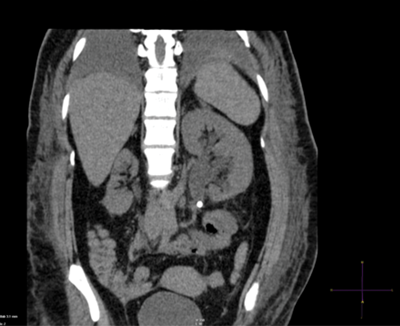

Case 4

- What imaging modality is this, what is the diagnosis?

- What is the radiation exposure for this study?

- What advantages does this study have over an IVU?

- What is the sensitivity and specificity for CT in diagnosing renal tract stones?

-

Plain CT KUB, coronal reconstruction demonstrating left PUJ stone with associated hydronephrosis.

4.5mSv

Quick scan (20-30 seconds), easy to interpret, no IV contrast needed, can establish differential diagnosis.

Sensitivity >95%, specificity >96%.